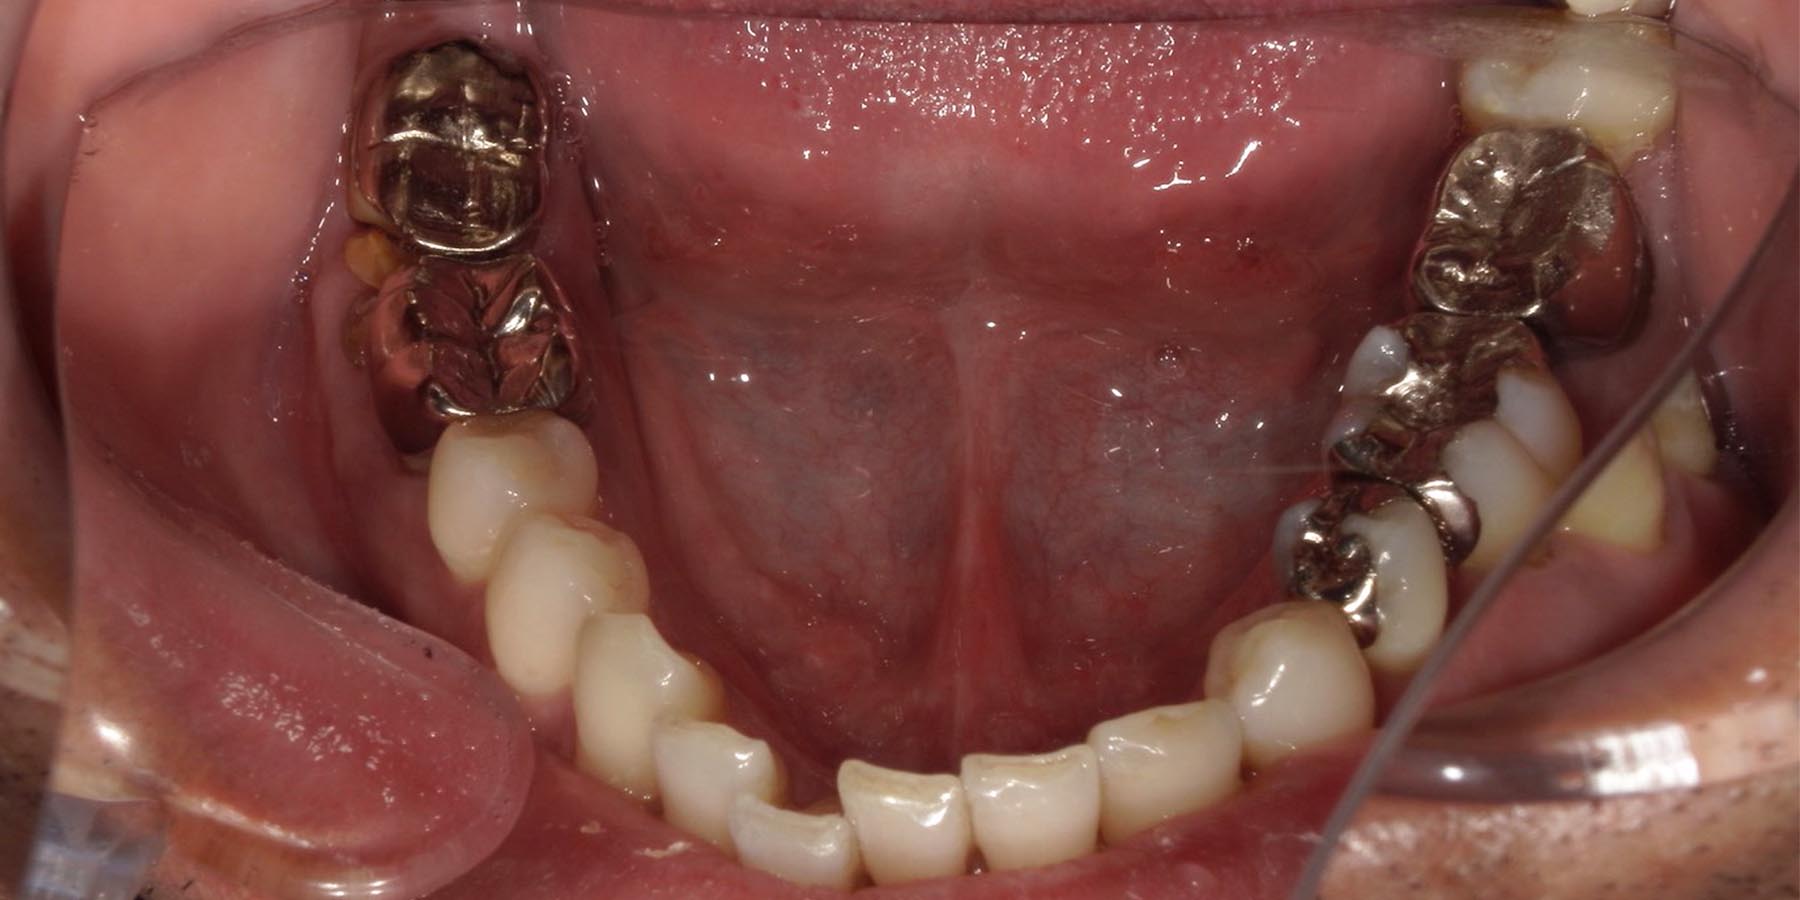

治療前